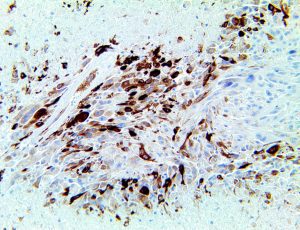

It is the ICU physician who is most likely to witness one of the deadliest manifestations of the abnormal immunological response, the cytokine storm syndrome (CSS). This response is also referred to by some as the cytokine release syndrome (CRS). CSS is characterized by continuous activation and expansion of macrophage and lymphocyte populations, which secrete large amounts of cytokines, causing the cytokine storm. This massive cytokine release is akin to hemophagocytic lymphohistiocytosis (HLH) disease, a syndrome characterized by initial unchecked and persistent activation of cytotoxic T lymphocytes and NK cells.

Clinical and laboratory manifestations of HLH include fever, enlarged liver and/or spleen, neurologic dysfunction, coagulopathy, liver dysfunction, cytopenias (i.e., low levels of erythrocytes, leukocytes, and/or platelets), hypertriglyceridemia, hyperferritinemia, hemophagocytosis, and eventually diminished NK cell activity as the immune system becomes progressively paralyzed. HLH can be familial (primary HLH) or secondary to another disease process (sHLH), such as rheumatic disease, in which it is referred to as macrophage activation syndrome (MAS, characterized by elevated ferritin).